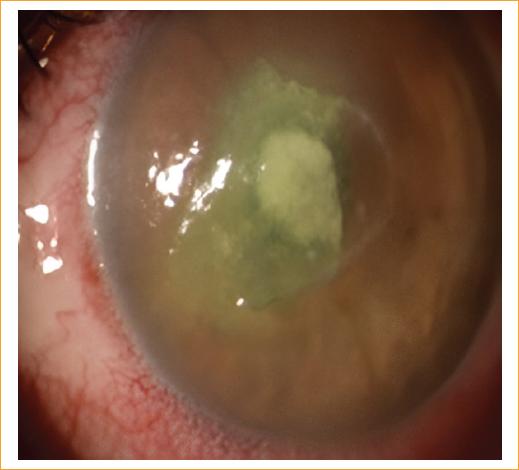

Varón de 45 años que consulta al servicio de urgencias por un cuadro clínico de 3 días de evolución consistente en dolor, ojo rojo, fotofobia y sensación de cuerpo extraño en el ojo izquierdo posterior al lavado de la cara con agua de tanque en un área rural. El paciente refiere estar aplicando gotas de lágrimas, sin mejoría de la sintomatología. Al examen oftalmológico de ingreso presenta una agudeza visual en el ojo derecho de 20/20 y en el ojo izquierdo de 20/400. En la biomicroscopia, el segmento anterior del ojo derecho está sano. En el ojo izquierdo se evidencia una importante hiperemia conjuntival con un defecto epitelial central de 5 × 5 mm que compromete el eje visual, con infiltrado intraestomal de 2 × 2 mm, de bordes plumosos, con lesiones satélite, infiltración en anillo y edema estromal perilesional, con tinción positiva a la fluoresceína (Figs. 1 y 2); el resto del segmento anterior del ojo izquierdo es normal. La presión intraocular del ojo derecho es de 12 mmHg y la del ojo izquierdo no se determina. La fundoscopia indirecta de ambos ojos es normal. Posteriormente se realiza raspado del absceso con hoja de bisturí del n.º 15, que se reserva en tubo de ensayo y es llevado al laboratorio de patología para ser examinado por el patólogo en el microscopio con tinción de hematoxilina-eosina.

Figura 1 Foto clínica del ojo izquierdo, con hallazgos de importante hiperemia conjuntival con un defecto epitelial central de 5 × 5 mm e infiltrado estromal de 2 × 2 mm de bordes plumosos, con lesiones satélite, infiltrado en anillo y edema estromal perilesional.